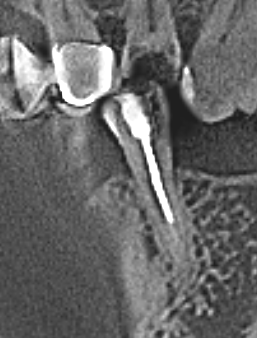

nau_63 Опубликовано 11 ноября, 2025 Поделиться Опубликовано 11 ноября, 2025 (изменено) Добрый день. Задавал вопрос по протезированию этого зуба в разделе Протезирование, но сейчас все идет к установке пломбы, а затем коронки. Поэтому прошу совета здесь. Нижняя 5-ка слева. Сильный клиновидный дефект, очевидно из-за отсутствующего соседнего зуба . Зуб депульпирован и для прочности установлен штифт. Сбоку была пломба, но быстро отвалилась. При надавливании на зуб в сторону языка есть не сильная боль (не понятна причина этой болезненности, зуб пролечен качественно. При жевании даже жесткой пищи чувствительности нет). Клиновидный дефект сильный. Но штифт не просвечивает, т.е. полость менее 50%. Так вот вопрос, каким материалом лучше запломбировать дефект? Увы, но разные врачи предлагают разные варианты. И может быть есть предположение, почему присутствуют болезненные ощущения при одном направлении давления. Изменено 11 ноября, 2025 пользователем nau_63 добавление картинки Ссылка на комментарий

nau_63 Опубликовано 12 ноября, 2025 Автор Поделиться Опубликовано 12 ноября, 2025 (изменено) Добавлю фото. Нижняя часть дефекты немного накрылась десной. Темный фон за зубом - это разрез от установленного 2 дня назад импланта. Изменено 12 ноября, 2025 пользователем nau_63 уточнение Ссылка на комментарий